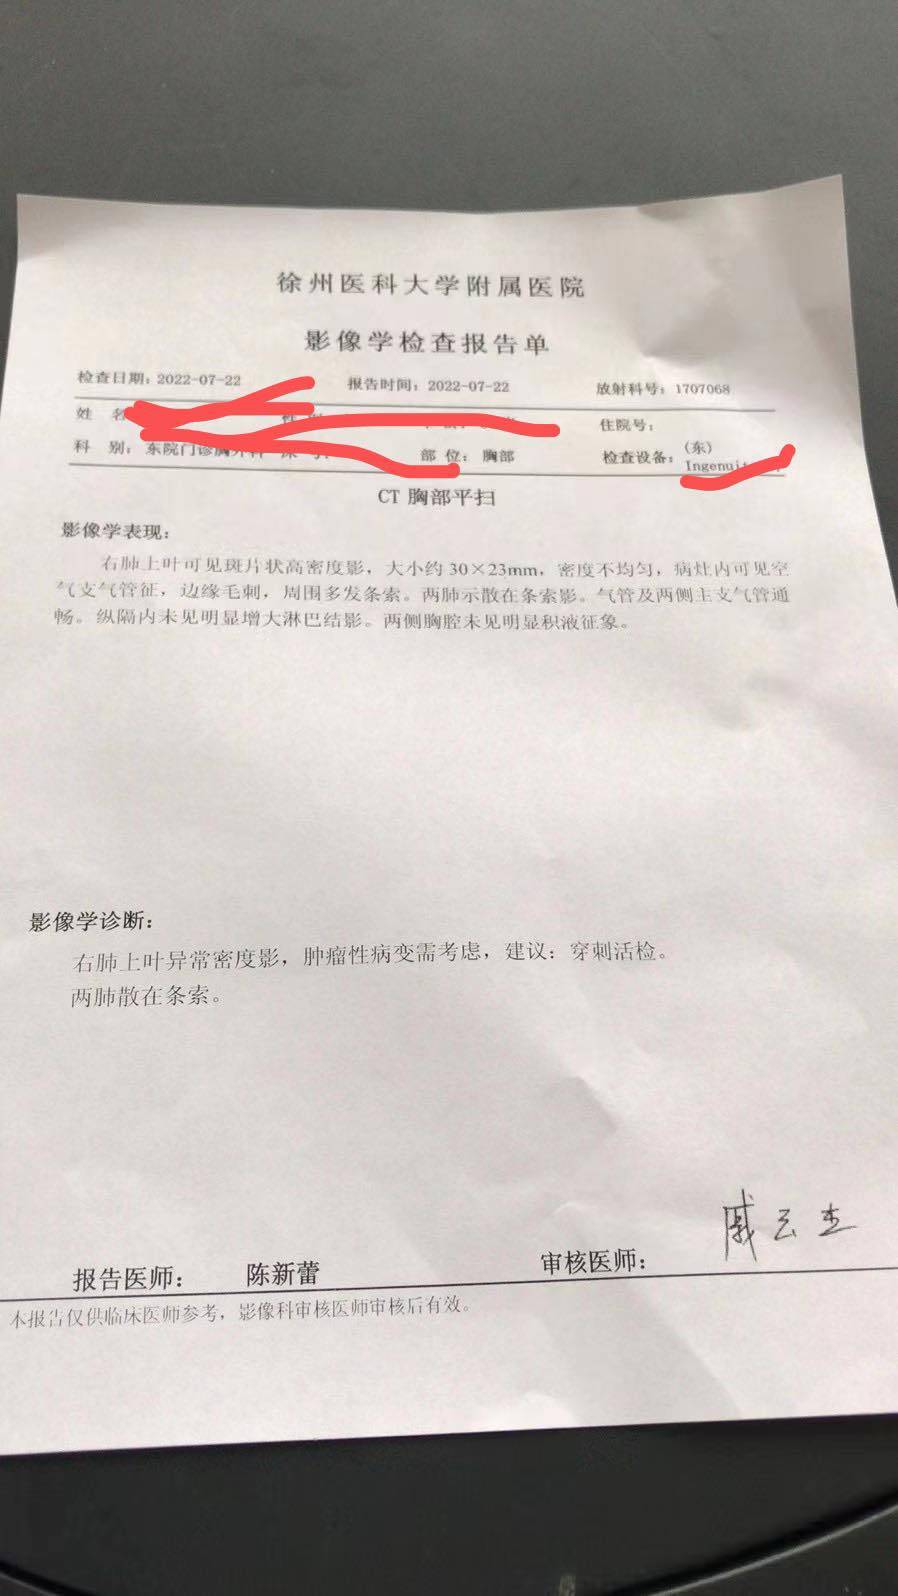

met14跳跃缺失

met14跳跃缺失有点家族史。。保险不要省。

有希望就会有奇迹我也是如此,去年爷爷查出胃癌,今年姑姑查出肝癌,父亲查出肺癌。真的有点崩溃了